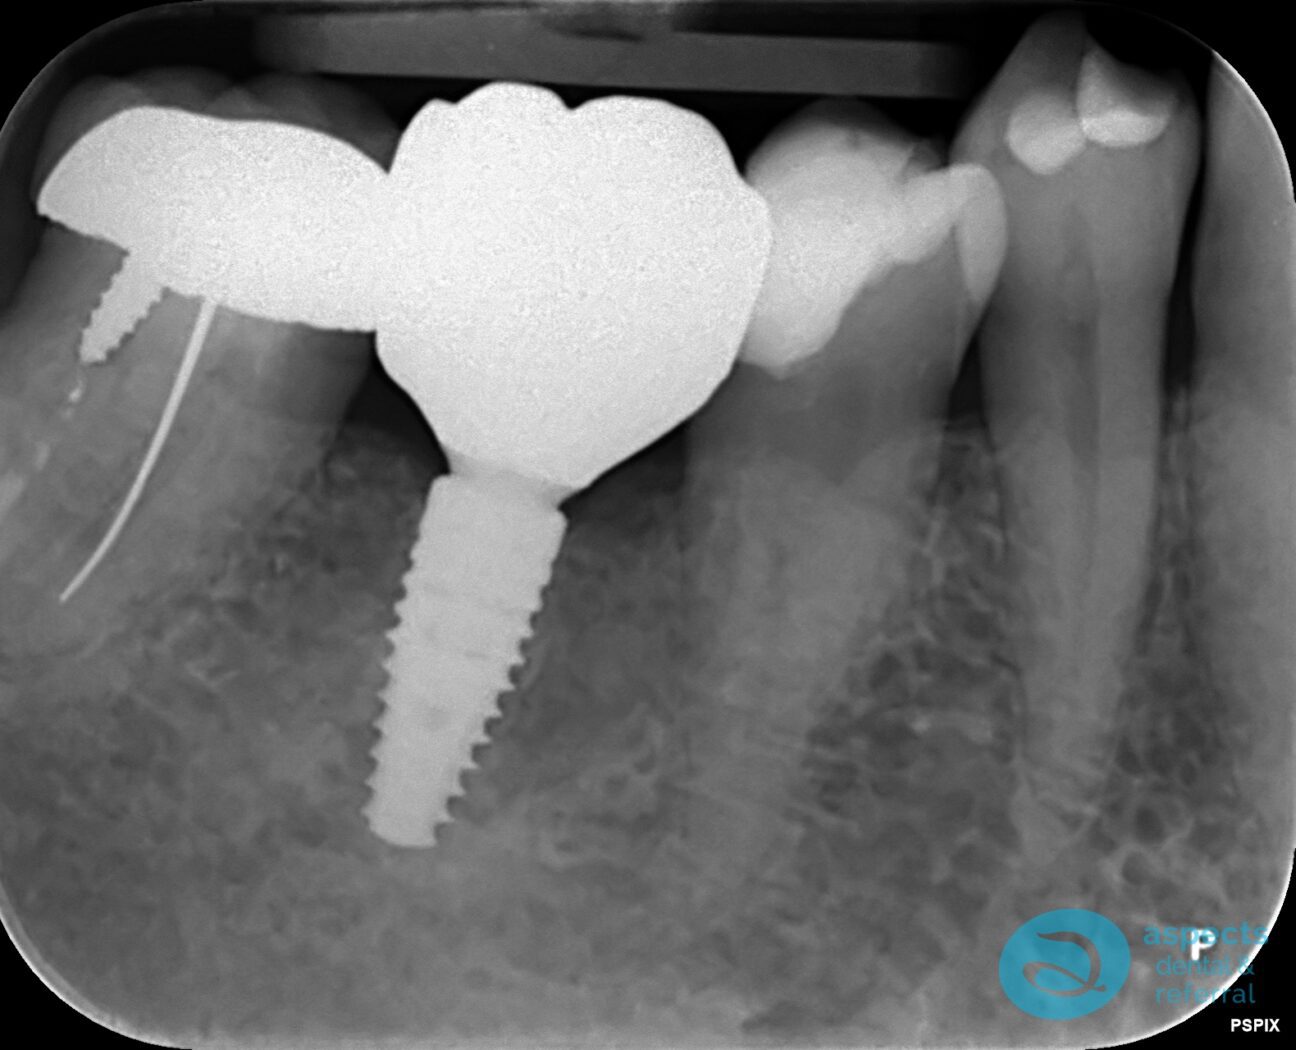

The tooth was extracted carefully, and following site preparation, a Dental Implant was placed in the extraction site. After an appropriate healing and osseointegration period, the implant was successfully restored with a definitive prosthesis, restoring function and aesthetics.

After Dental Implant Xray